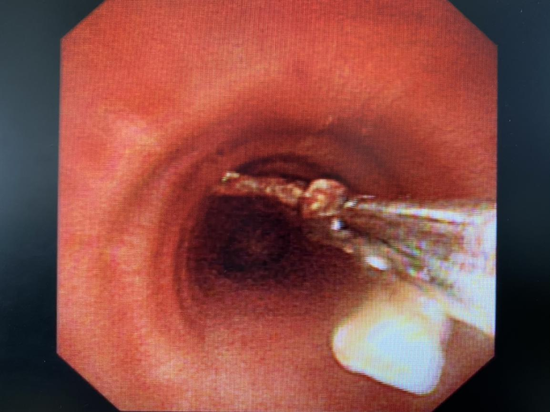

他发现,她左肺下叶支气管开口处,真的有个条状的、灰黑色的异物!

周边还有大量肉芽组织增生,导致气管结构改变。

黄绿色的脓痰,死死地堵住了管腔。

几分钟后,医生取出了这个东西,仔细一看,竟然是一块“带刺”的鸡骨头。

呼吸内科顾问医生荣磊使用异物钳夹出“罪犯”异物

这折磨了蔡女士多年的鸡骨头,长达20mm,边角还十分锐利。

更要命的是,骨头的尖端,距离主动脉只有6.3mm!